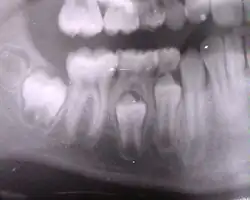

La première dent définitive fait son éruption vers 5-6 ans : c'est la première molaire ("dent de 6 ans"). La dernière vers 12-13 ans ; c'est généralement une prémolaire sans compter les dents de sagesse inconstantes pouvant apparaître jusqu'à 25 ans.

| Dents permanentes | Âge |

|---|---|

| incisives centrales | 7 - 8 ans |

| incisives latérales inférieures | 7 - 8 ans |

| incisives latérales supérieures | 8 - 9 ans |

| canines inférieures | 9 - 10 ans |

| canines supérieures | 11 - 12 ans |

| premières prémolaires | 10 - 11 ans |

| deuxième prémolaires | 10 - 12 ans |

| premières molaires | 5 - 6 ans |

| deuxièmes molaires | 12 - 13 ans |

| troisièmes molaires | 15 - 25 ans |